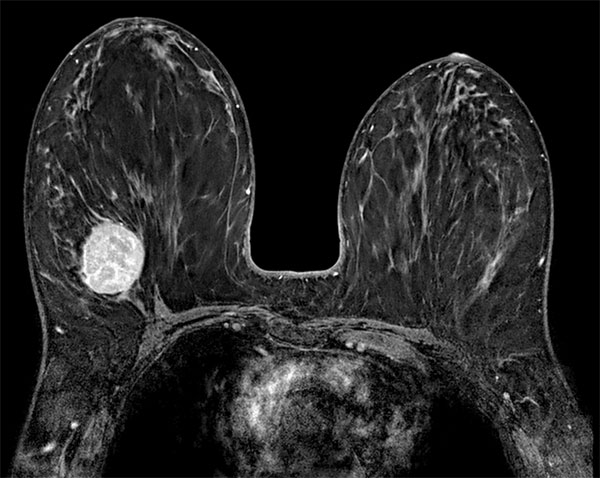

SmartBreast - dS Breast 7ch coil

Utrecht Medical Center, The Netherlands

Used Solution

• System

• Coil